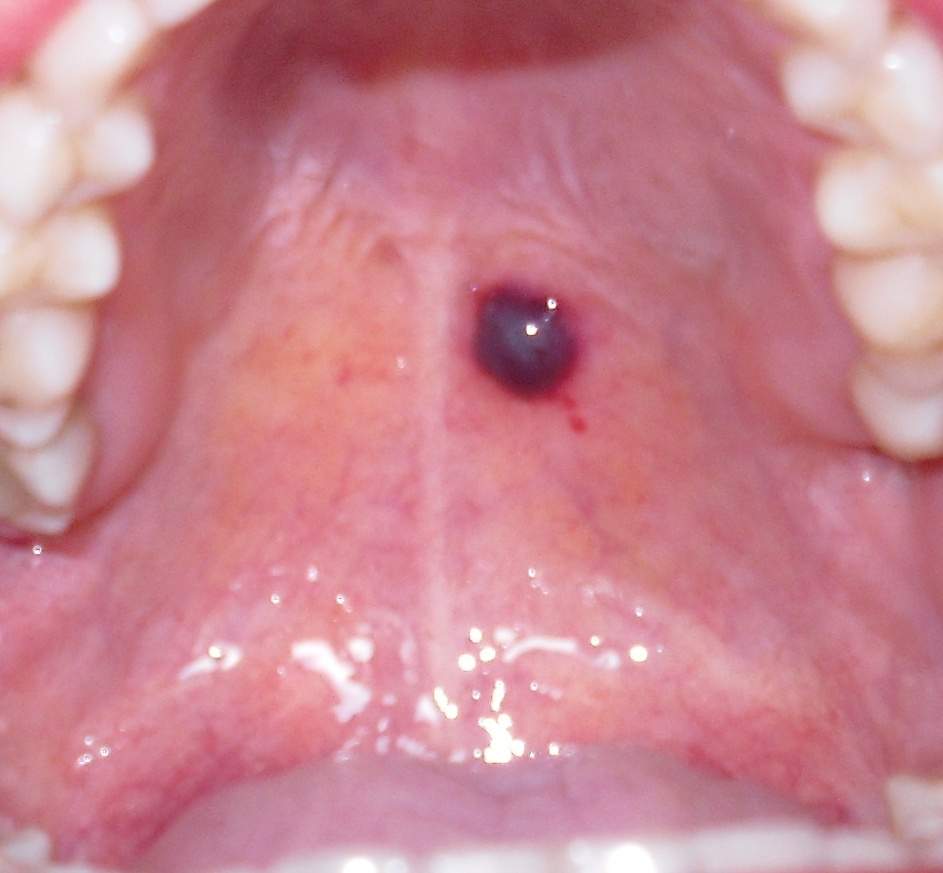

Schwarzer punkt im Mundraum bekommen was ist das siehe ( Bild )? (Gesundheit, Gesundheit und

Dunkle Wunde in Mundhöhle (Gesundheit, Medizin, Arzt)